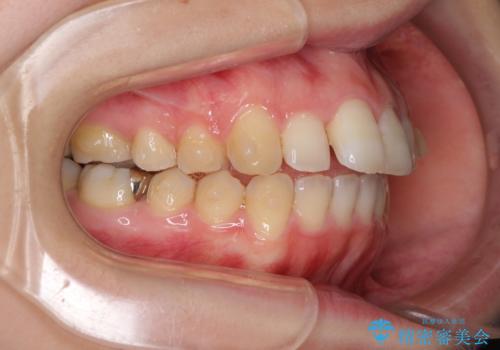

割れてしまった奥歯は抜歯し、矯正治療中の良いタイミングでインプラントを埋入することとしました。

インプラントは、治療期間を短くすることが可能な、ストローマン社のSLActiveを使用することとしました。